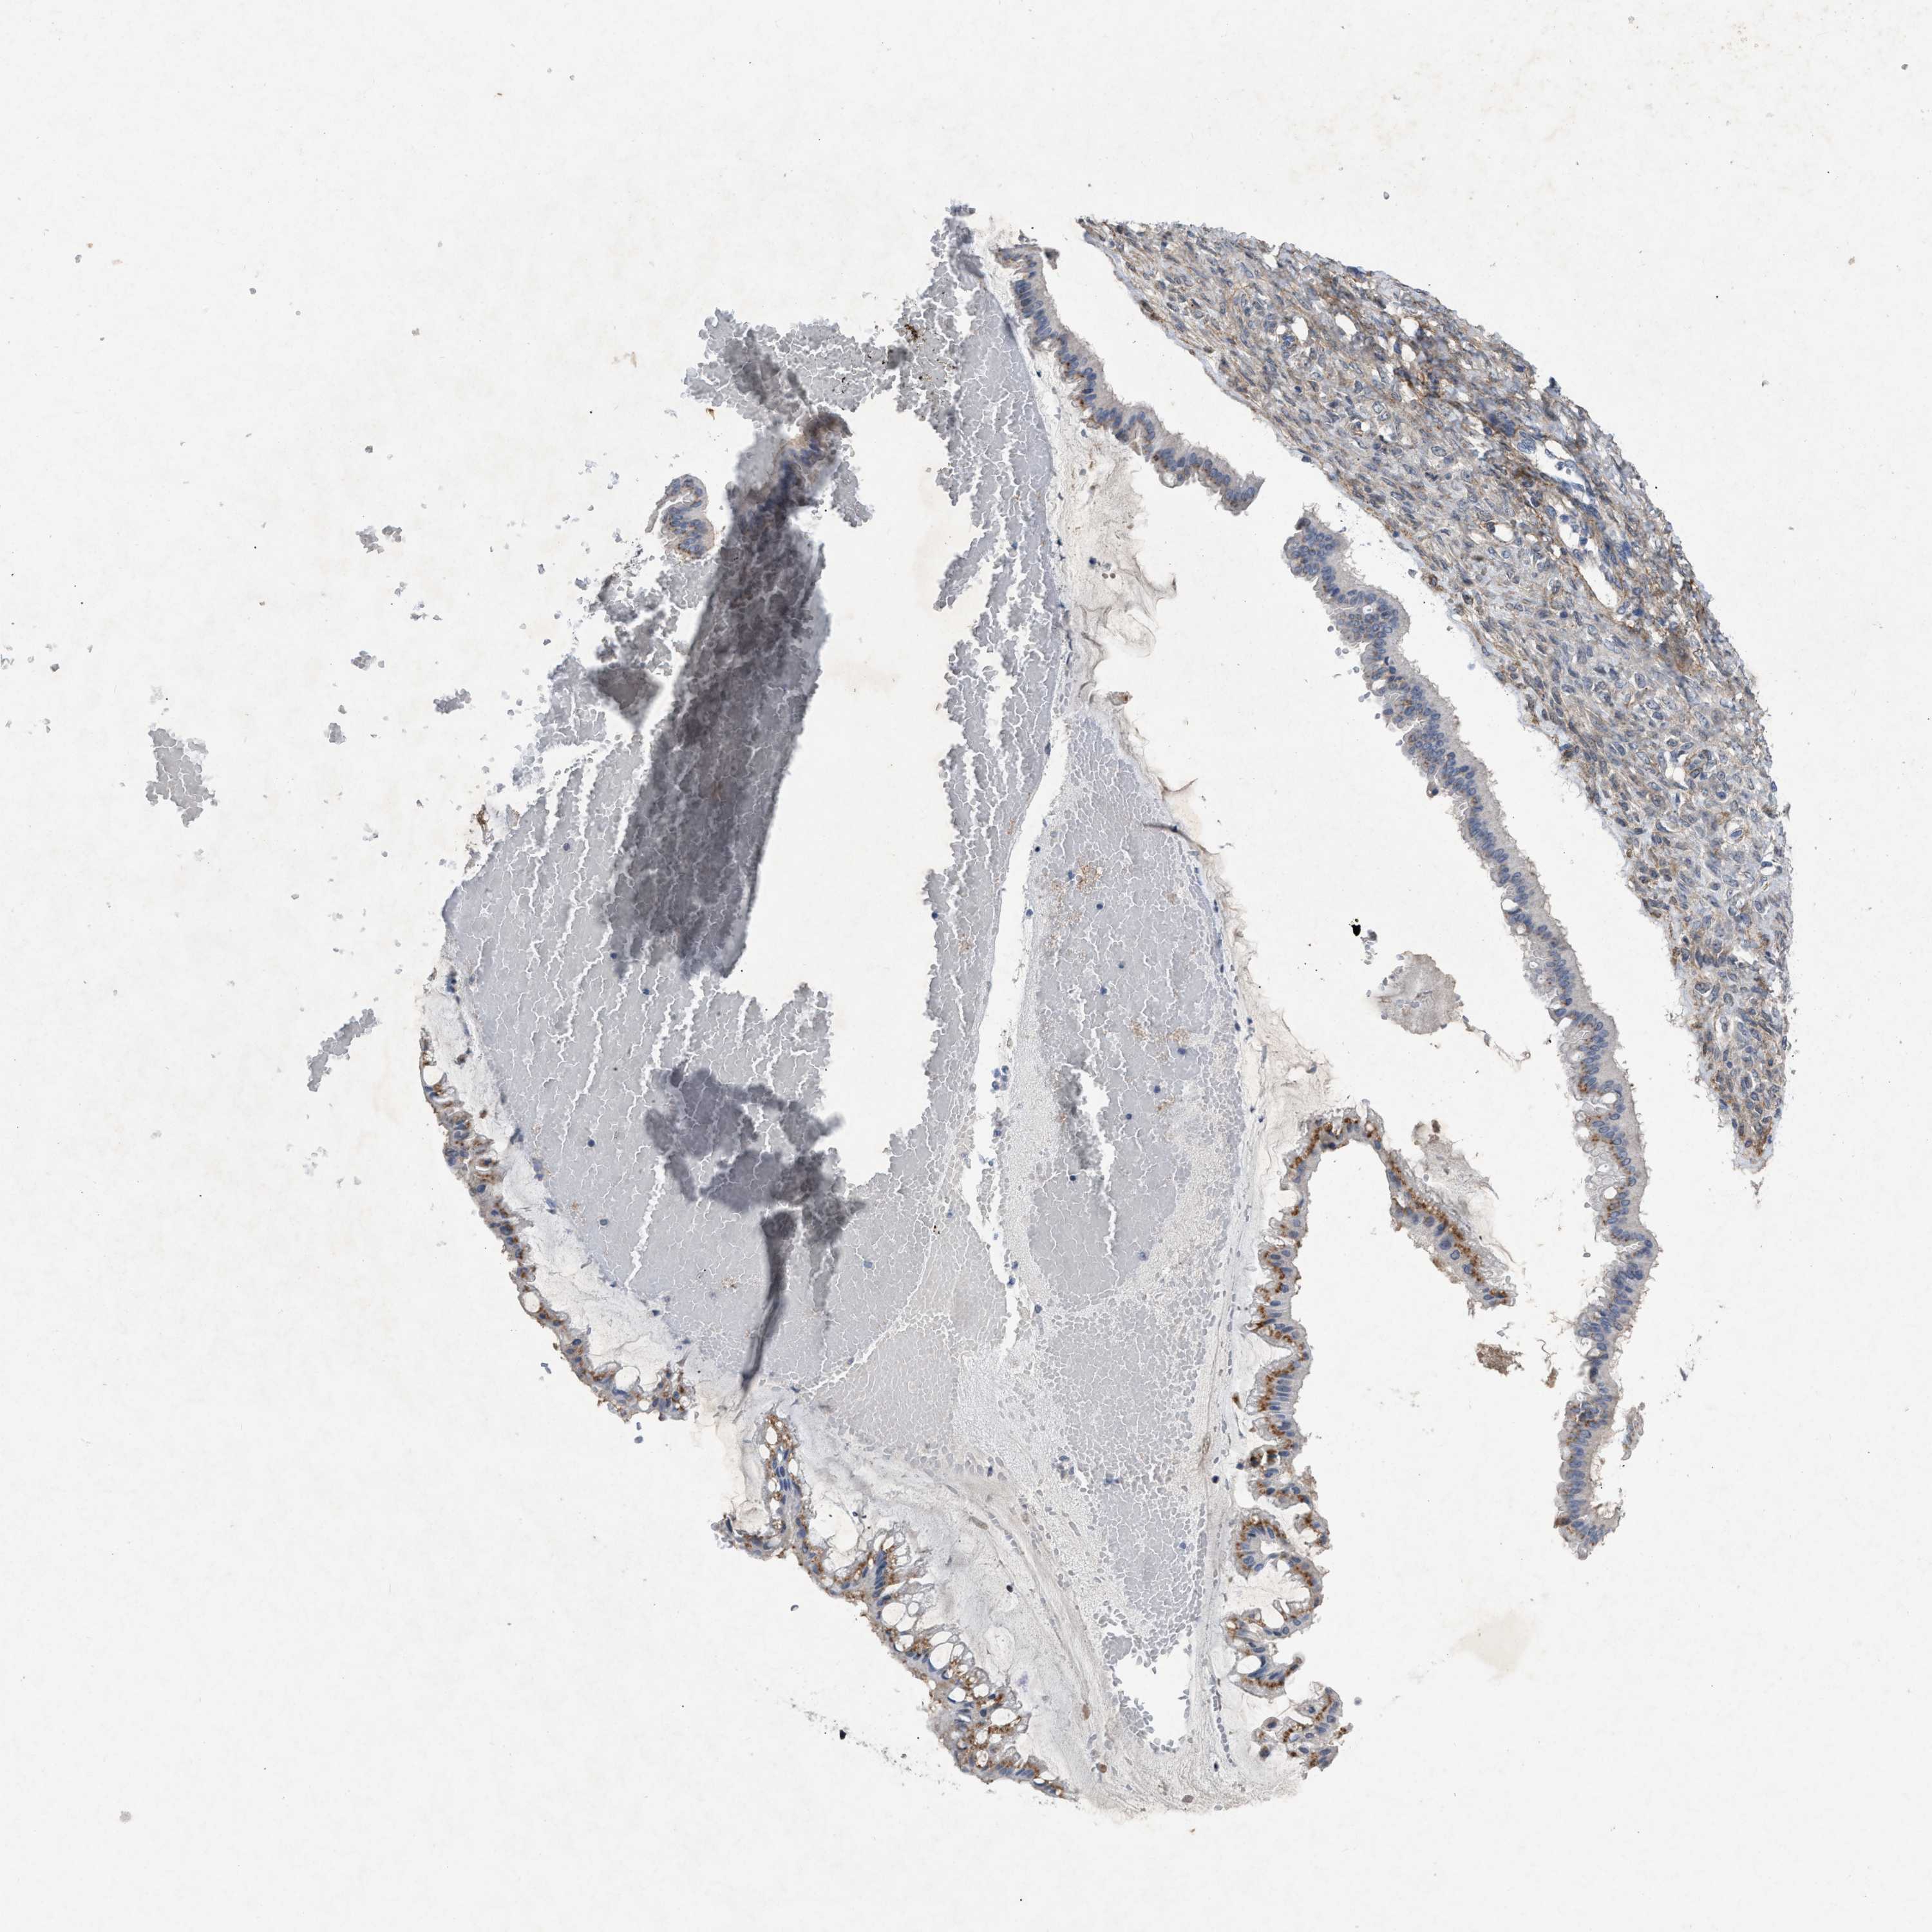

OVARIAN CANCER - Protein expressioni

A mouse-over function shows sample information and annotation data. Click on an image to view it in a full screen mode. Samples can be filtered based on level of antibody staining by selecting one or several of the following categories: high, medium, low and not detected. The assay and annotation is described here.

Note that samples used for immunohistochemistry by the Human Protein Atlas do not correspond to samples in the TCGA dataset.

Antibody stainingi

Antibody staining in the annotated cell types in the current human tissue is reported as not detected, low, medium, or high, based on conventional immunohistochemistry profiling in selected tissues. This score is based on the combination of the staining intensity and fraction of stained cells.

Each image is clickable and will lead to virtual microscopy that enables deeper exploration of all samples and also displays staining intensity scores, fraction scores and subcellular localization as well as patient and tissue information for each sample.

Antibody CAB018143

Staining

High

Medium

Low

Not detected

Intensity

Strong

Moderate

Weak

Negative

Quantity

>75%

75%-25%

<25%

None

Location

Nuclear

Cytoplasmic/membranous

Cytoplasmic/membranous,nuclear

Cystadenocarcinoma, serous, NOS

Carcinoma, endometroid

Cystadenocarcinoma, mucinous, NOS

Carcinoma, NOS